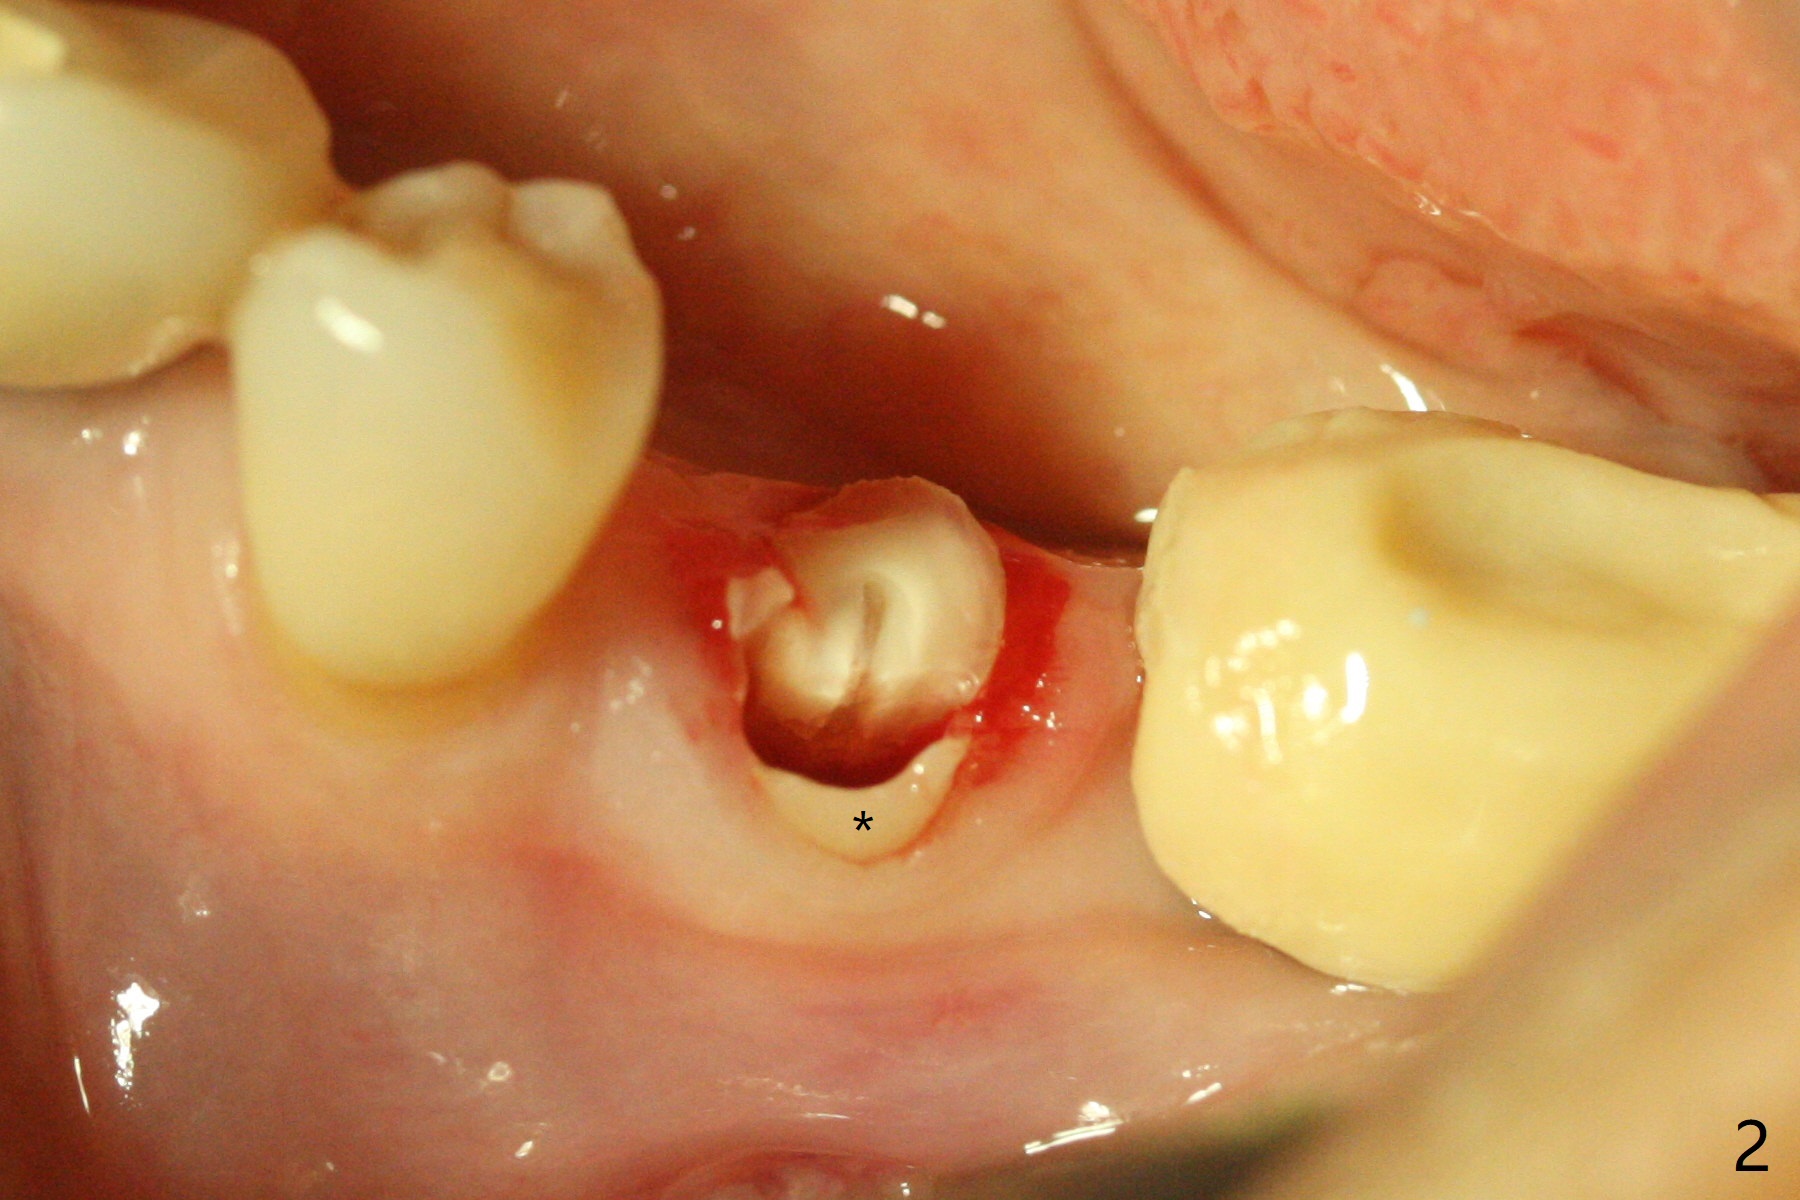

Socket Shield is conducted at #20 (Fig.1-3 *). With placement of a 4x11.5 mm implant equicrestal lingually, a 4.5x6(2) mm temporary abutment is unable to be seated incompletely (Fig.4 black <) because of proximal crestal interference (white arrowheads). After use of a 5.5 mm profile drill, a 5.5x5 mm healing abutment is apparently seated completely (Fig.5). Upon close look, the abutment at #19 is also incompletely seated. In fact #18/19 temporary crowns and #19 abutment are loose. A 6.8x4 mm healing abutment is later placed at #19. Periodontal dressing is applied at #18-20. In fact buccolingual control of osteotomy is not easy with free hand. A smaller implant (e.g., 3.5 mm) may be easier.